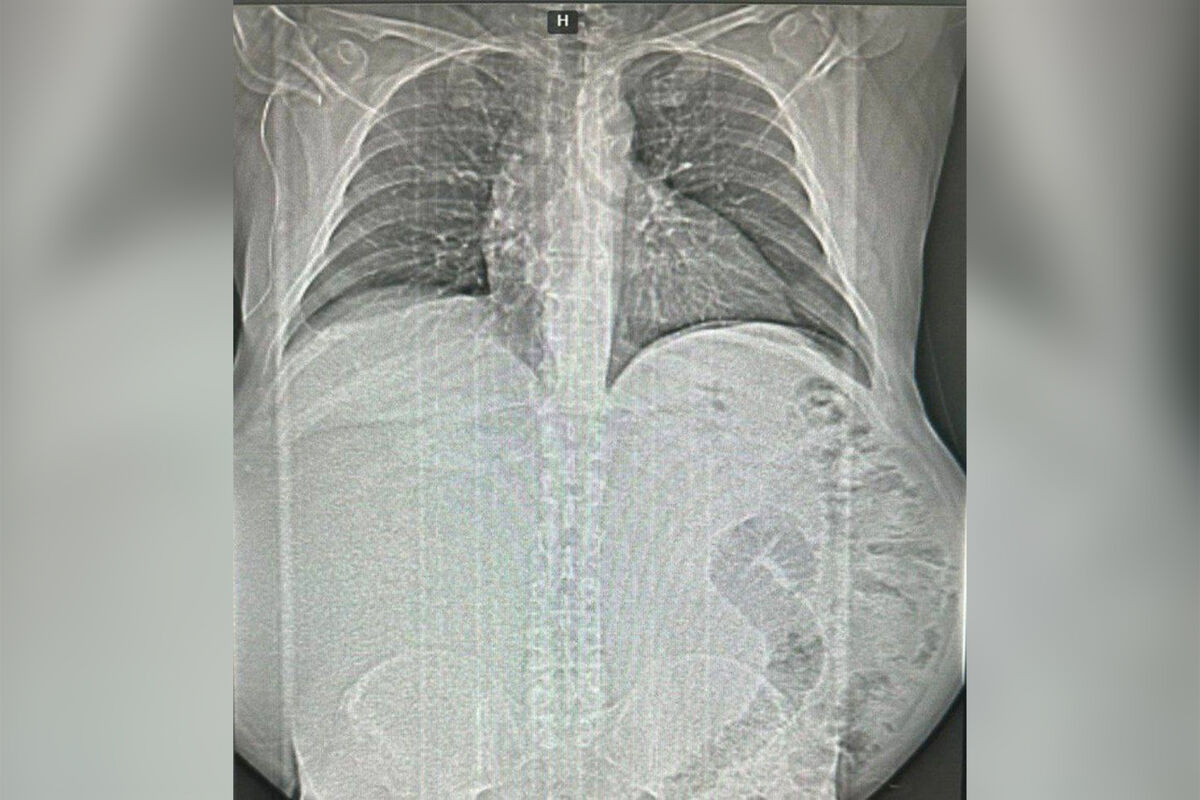

Россиянин не обращался к врачам и вырастил 17-килограммовую опухоль

В Краснодаре спасли мужчину с 17-килограммовой опухолью в животе

Врачи Краевой rлинической больницы №1 имени профессора С.В. Очаповского спасли пациента, удалив ему гигантскую опухоль. Об этом министр здравоохранения Краснодарского края Евгений Филиппов сообщил в своем Telegram-канале.

Как рассказал глава ведомства, пациент активно болел около года — он стремительно набирал вес, но не обращался за помощью, так как развивавшееся образование не мешало жить. Во время диагностики медики нашли у пациента объемное новообразование в брюшной полости.

Операция по удалению новообразования длилась четыре часа. Вес опухоли составил около 17 килограммов.